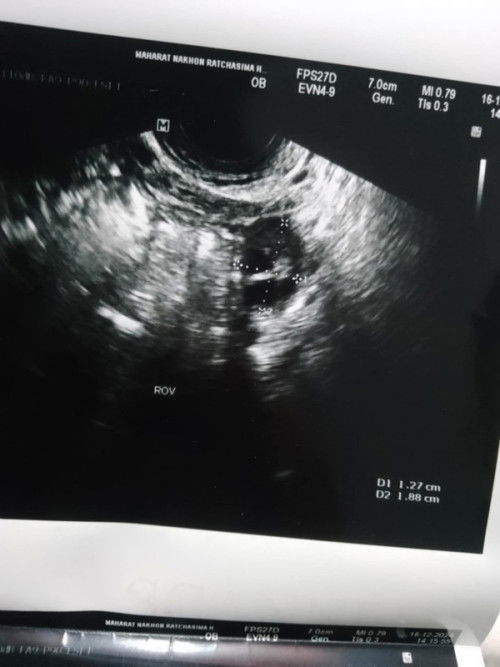

สอบถามแม่ๆหน่อยค่ะพอดีตรวจที่โรงบาลโชคชัยใหม่กับโรงบาลปักพบถุงการตั้งครรภ์แต่มาตรวจมหาราชไม่เจออะไรเลยหมอบอกไม่ได้ท้อง😢คือยังไงหรอคะ แม่ๆคนไหนเคยเป็นแบบนี้บ้างตรวจอีกโรงบาลเจออีกโรงบาลไม่เจอ#ขอบคุณล่วงหน้าสำหรับความคิดเห็นค่ะ

ใช่ถุงการตั้งครรภ์ไหมคะ

หมอบอกน้อง4สัปดาห์และมีเลือดออก หมอบอกการฝังตัวอ่อนค่ะ เป็นได้ปกติพบได้บ่อยคุณแม่ตั้งครรภ์อ่อนแรกๆ#ขอบคุณล่วงหน้าสำหรับความคิดเห็นค่ะ รึเป็นเลือดค้าง

ใช่ถุงการตั้งครรภ์ไหมคะ หมอบอกว่า4สัปดาห์ มีเลือดออกหมอบอกปกติของการฝังตัวอ่อน🥹แม่กังวลมากค่ะกลัวน้องไม่อยู่ด้วย